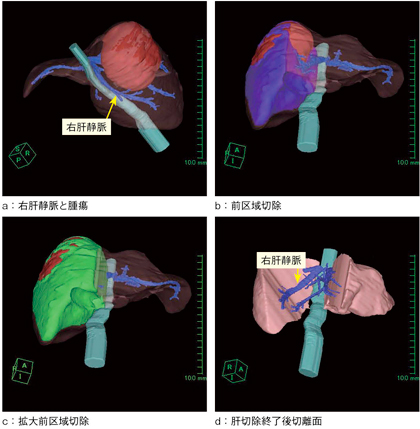

図3 術前シミュレーション

右肝静脈は腫瘍と離れておりintactであることがわかる(a)。前区域切除では腫瘍が切離面に露出する(b)ため,中肝静脈を切除する拡大前区域切除(c)の予定となった。dは切除後の肝切離面。